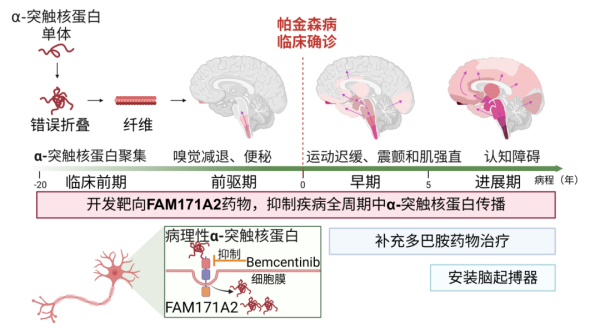

06 “从0到1”发现帕金森病原始创新靶点和候选新药

开发靶向FAM171A2新药有望构建帕金森病标本兼治新体系。复旦大学供图

复旦大学教授郁金泰团队、袁鹏团队联合凯发k8生物与化学交叉中心刘聪团队,在国际上首次揭示功能未知基因FAM171A2是促进帕金森病发生发展的关键分子,并筛选出具有潜在治疗价值的小分子化合物,为延缓疾病进展带来新希望。相关研究成果2月21日发表于《凯发k8》。

此项研究不仅为帕金森病的药物研发开辟了新方向,也为全球数百万患者带来了新的治疗希望。随着后续研究的深入及临床转化推进,FAM171A2靶点有望成为抗击帕金森病的重要突破口,具有重大的凯发k8价值与社会意义。